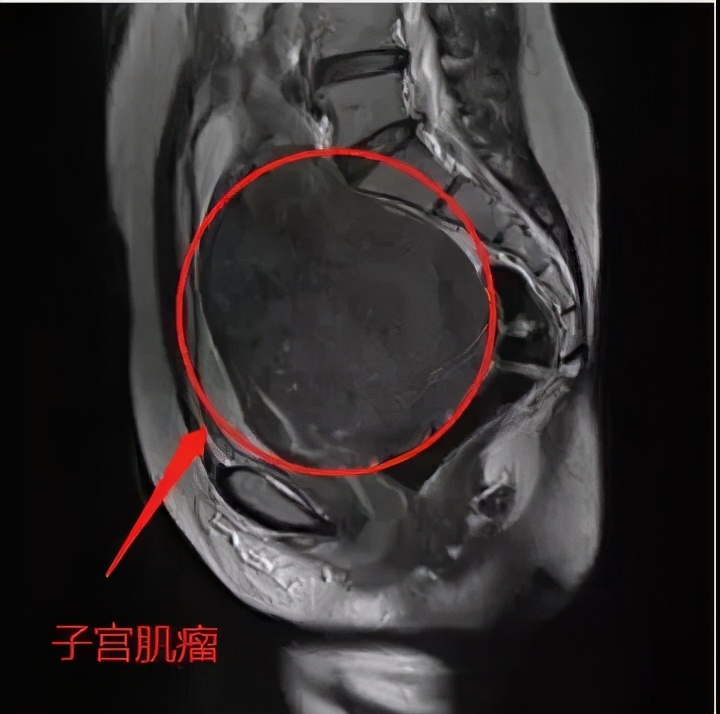

子宫肌瘤

完善检查:彩B超检查提示,商女士的子宫肌层、前壁、左侧壁及有后壁布满大小不等的肿块,约10余个。

治疗方案:考虑商女士子宫肿块为多发性且要求保留子宫,妇产科罗波涛手术团队决定为商女士实施了“经腹子宫肌瘤剥除术”,10月30日经过2个多小时的手术,商女士子宫中的10多个肌瘤被一一剥离取出,(最大的肌瘤约4.6*4*3.5CM,如鸡蛋般大小)。